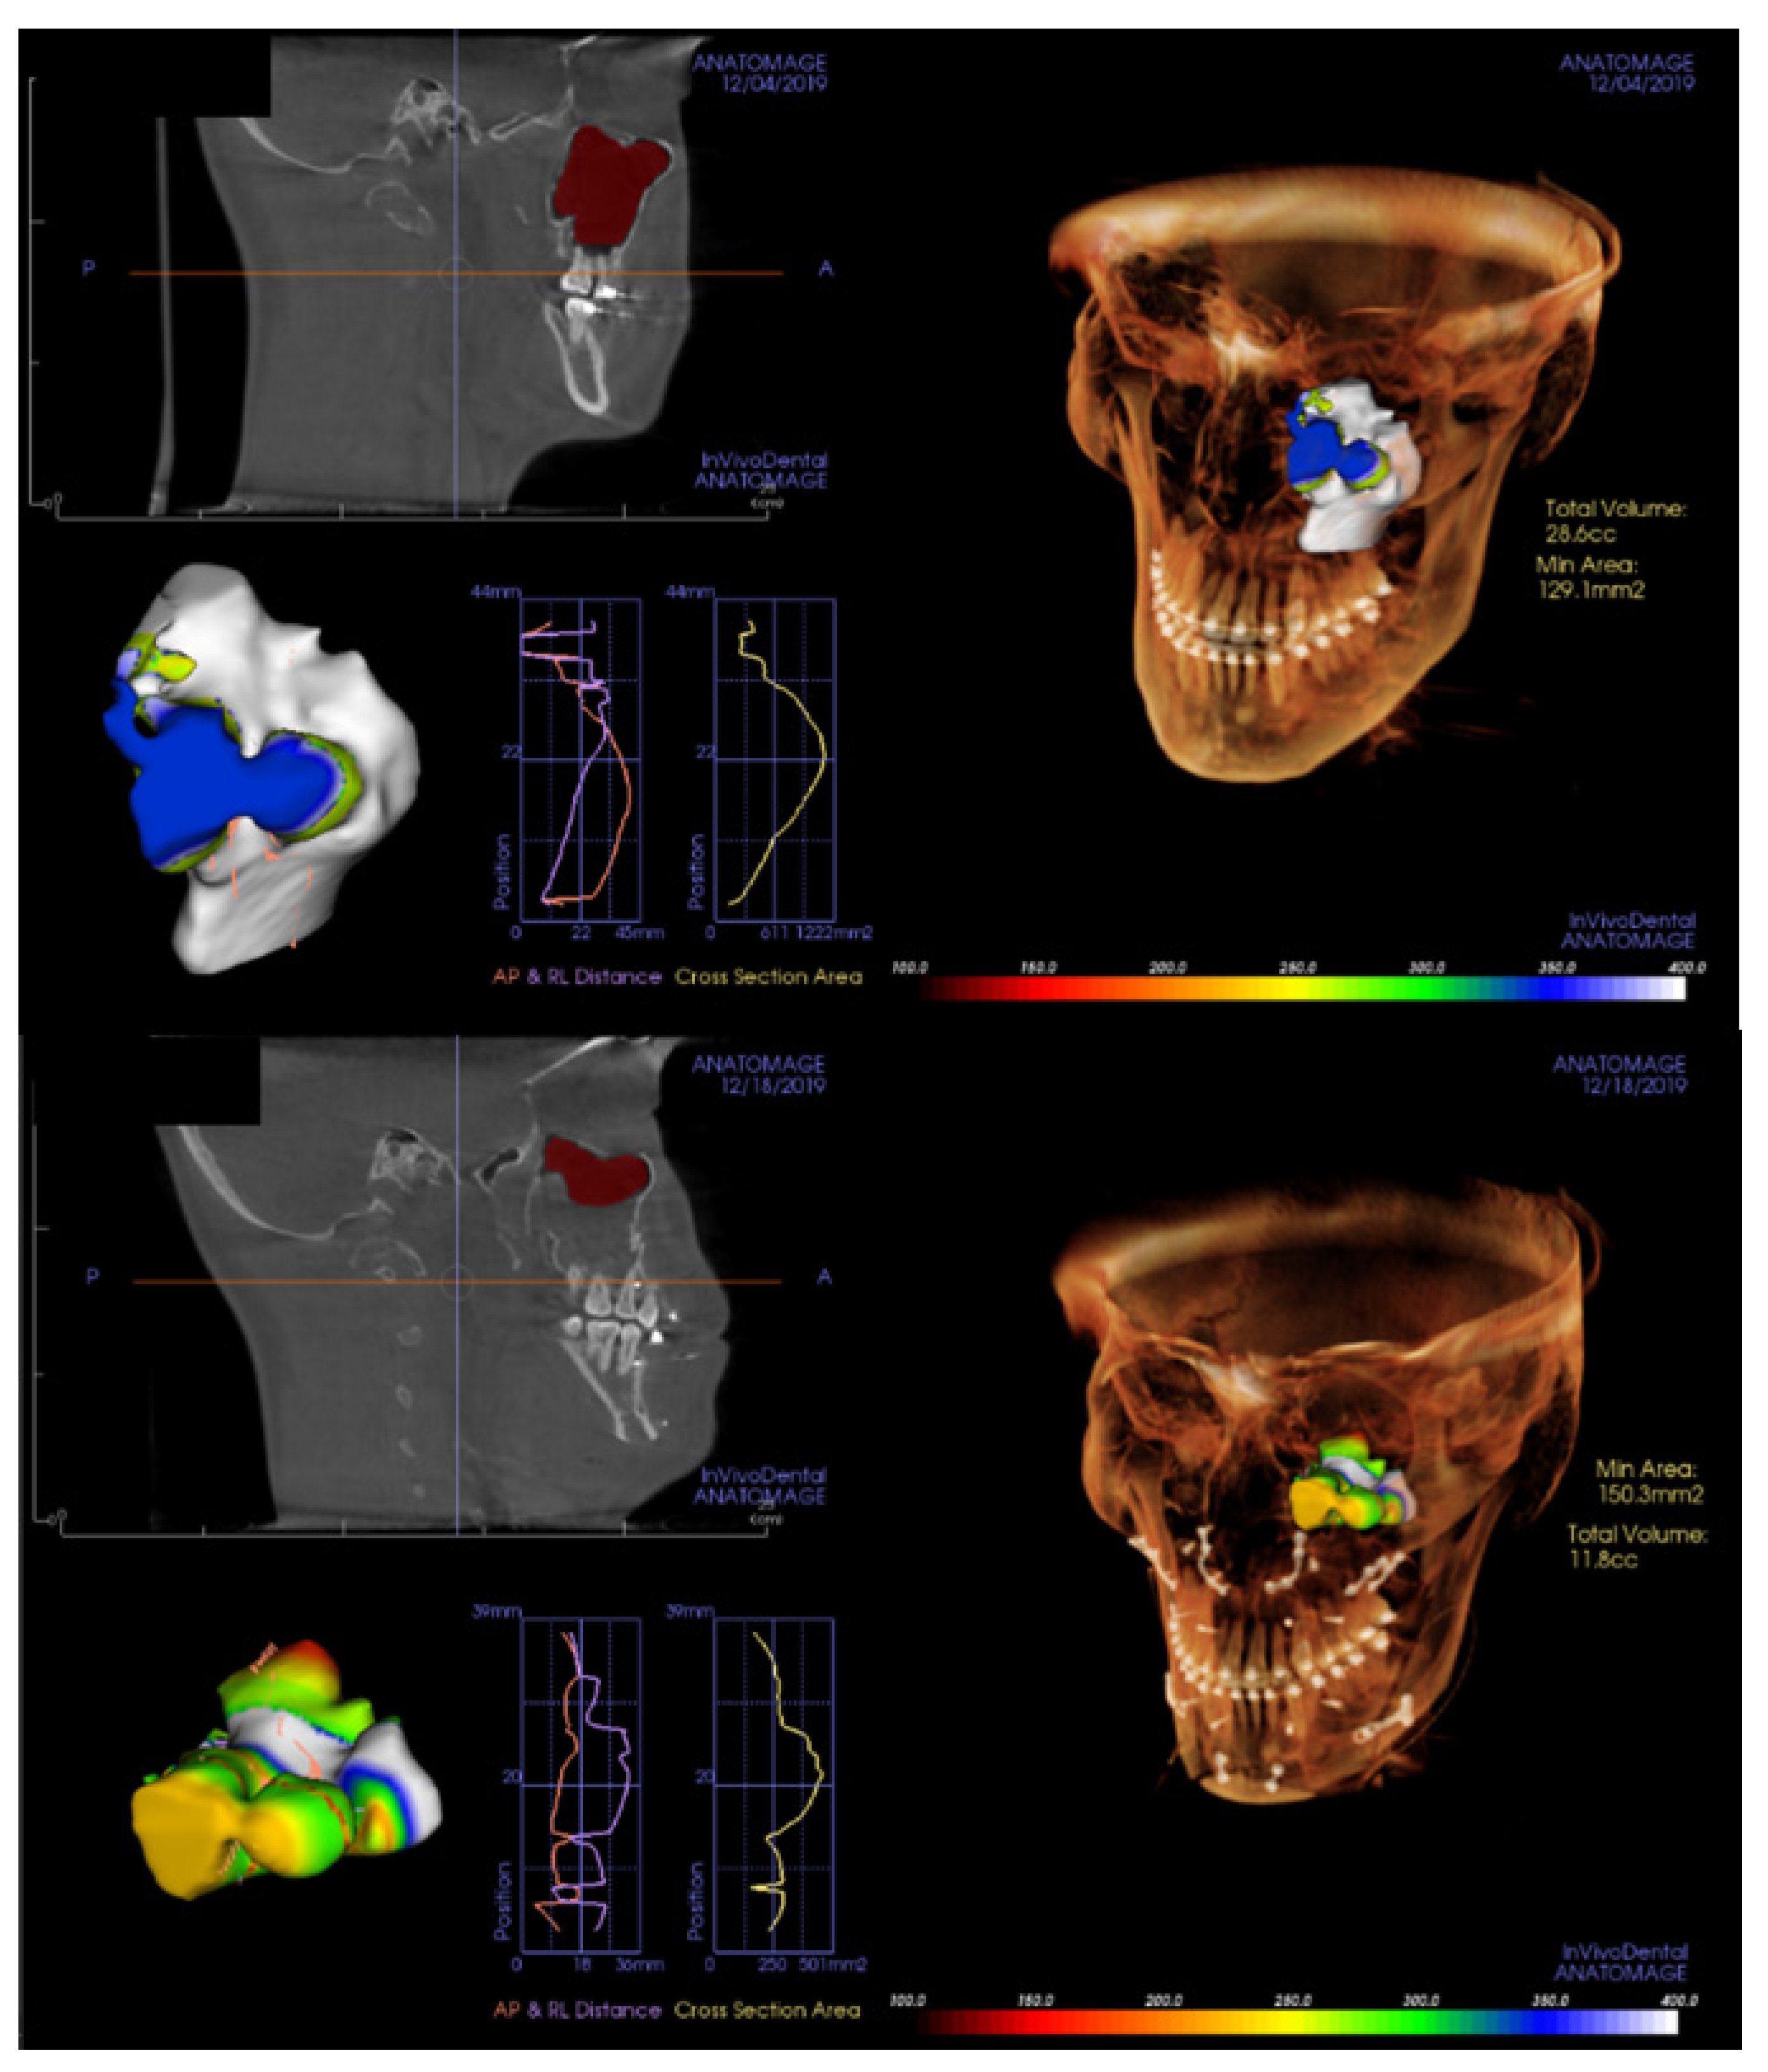

2.2. Radiological Analysis

3. Results